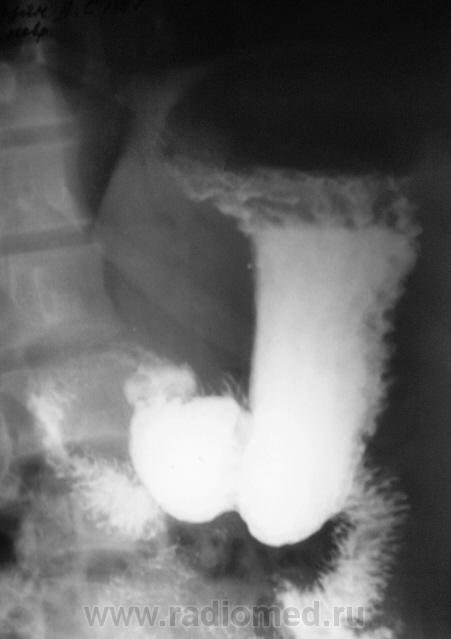

Вообще довольно часто встречающаяся ситуация с военкоматом, когда эндоскосписты, что-то нашли, а "рентген" не нашел. Но в данном случае наоборот - эндоскописты кроме "гастритика" ничего не нашли, рентгенологи дали заключение о наличии язвенной болезни 12-ти перстной кишки. Что делать терапевту, который будет писать акт, что делать эксперту, который будет выносить решение?

Принесли вот такие сгимки, спрашивают мнение.

"Язва" луковицы есть.....и на "рельефе" и на "конутре" "ниша" просматривается. Может у кого то будет другое мнение. послушаем.

На всей серии снимков формально - ниша в луковице. Однако на всех же снимках она хорошо заполнена, нет раздражения - главного косвенного признака... Возможно это в гипотонии? А в заключение - рубцовая деформация...

Релаксация не проводилась.